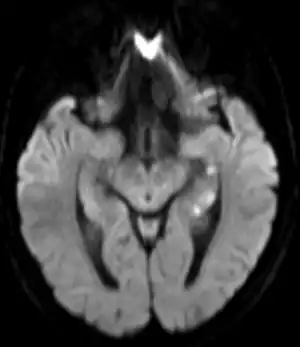

| Abnormal hippocampus findings consistent with transient global amnesia on MRI | |

.png.webp)

Unless there are concerning features, limited testing is required.[1] Medical imaging and lumbar puncture are generally not required.[1]

Recently, moreover, both imaging and neurocognitive testing studies question whether TGA is as benign as has been thought. MRI scans of the brain in one study showed that among people who had experienced TGA, all had cavities in the hippocampus, and these cavities were far more numerous, larger, and more suggestive of pathological damage than in either healthy controls or a large control group of people with tumor or stroke.[15] Verbal and cognitive impairments have been observed days after TGA attacks, of such severity that the researchers estimated the effects would be unlikely to resolve within a short time frame.[16] A large neurocognitive study of patients more than a year after their attack has shown persistent effects consistent with amnestic mild cognitive impairment (MCI-a) in a third of the people who had experienced TGA.[37] In another study, "selective cognitive dysfunctions after the clinical recovery" were observed, suggesting a prefrontal impairment.[13] These dysfunctions may not be in memory per se but in retrieval, in which speed of access is part of the problem among people who have had TGA and experience ongoing memory problems.[12]